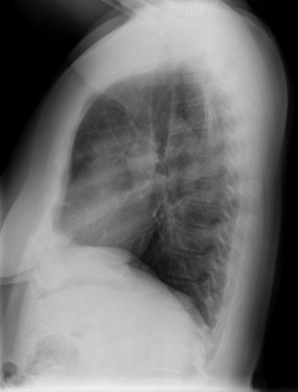

CASO: Febrícula y tos de 4 días de evolución.

Hallazgos:

- En la placa PA se observa una asimetría en los hilios pulmonares, el hilio izquierdo tiene una densidad aumentada.

- Tras examinar la placa lateral se observa un aumento de densidad en la columna que puede ser compatible con una condensación, es el signo de la desnificación vertebral.

SIGNO DE LA DENSIFICACIÓN VERTEBRAL: En la radiografía lateral normal, la densidad de la columna torácica tiende a disminuir desde la parte superior hasta el diafragma; la alteración de ese patrón por la presencia de una densidad superpuesta a la columna, indica la existencia de una consolidación pulmonar. Este signo adquiere especial valor cuando en la proyección posteroanterior la consolidación está oculta en el espacio retrocardíaco o en la base pulmonar.